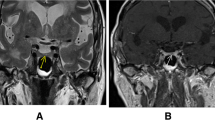

The results of the cerebral atrophy rating scale assessment before and after adjusting for SBP and BMI are shown in Table 2. Compared with NFA after adjustment, the subjects in the CD group showed decreased hippocampal height (P < 0.01) and increased temporal horn width (P < 0.01), suggesting temporal lobe atrophy in the CD patients (Fig. 1A, B). Increasing sylvian fissure ratio (SFR) (P < 0.01) and frontal interhemispheric fissure ratio (FFR) (P < 0.01) indicated cortical atrophy, while increasing bicaudate ratio (BCR) (P = 0.012) indicated subcortical atrophy in the CD patients, accompanied by widened third ventricle (P < 0.01) (Fig. 1C). Furthermore, the patients with CD tended to have more lacunar infarcts than NFA subjects (8/101 vs. 2/95, P = 0.055).

(A) MRI Image of a 43-year-old female CD patient with hippocampal atrophy compared with NFA subject; (B) MRI Image of a 45-year-old female CD patient with temporal lobe atrophy compared with NFA subject; (C) MRI Image of a 40-year-old female CD patient with subcortical atrophy compared with NFA subject.